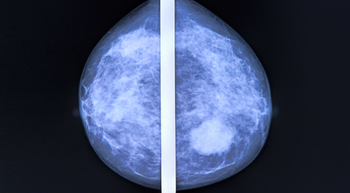

An observational study found no association between single-agent vaginal estrogen therapy or menopausal hormone therapy and increased risk of recurrence or mortality in patients with breast cancer.